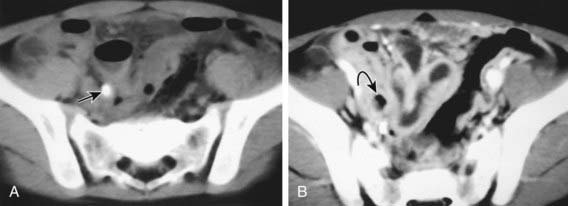

Ultrasound (US) is often used in the evaluation of acute appendicitis and has demonstrated >90% sensitivity and specificity in pediatric centers experienced with the technique. Graded abdominal compression is used to displace the cecum and ascending colon and identify the appendix, which has a typical target appearance (Fig. 335-2). The ultrasound criteria for appendicitis include wall thickness ≥6 mm, luminal distention, lack of compressibility, a complex mass in the RLQ, or a fecalith. The visualized appendix usually coincides with the site of localized pain and tenderness. Findings that suggest advanced appendicitis on ultrasound include asymmetric wall thickening, abscess formation, associated free intraperitoneal fluid, surrounding tissue edema, and decreased local tenderness to compression.

image

Figure 335-2 Ultrasound examination of patients with appendicitis. A, Transverse ultrasound scan of the appendix demonstrates the characteristic “target sign.” In this case, the innermost portion is sonolucent, compatible with fluid or pus. B, Longitudinal view of another patient demonstrates the alternating hyperechoic and hypoechoic layers with an outermost hypoechoic layer, suggesting periappendiceal fluid. C, Longitudinal ultrasound scan of the right lower quadrant (RLQ) demonstrates a dilated, noncompressible appendix. The bright echo within the appendix represents an appendicolith with acoustic shadowing (arrow).

(From Kuhn JP, Slovis TL, Haller JO: Caffrey’s pediatric diagnostic imaging, vol 2, ed 10, Philadelphia, 2004, Mosby, p 1684.)